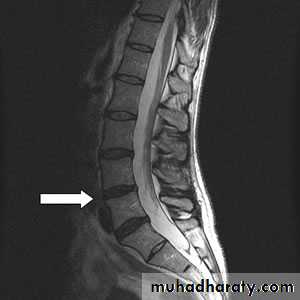

6.Spondylolisthesis